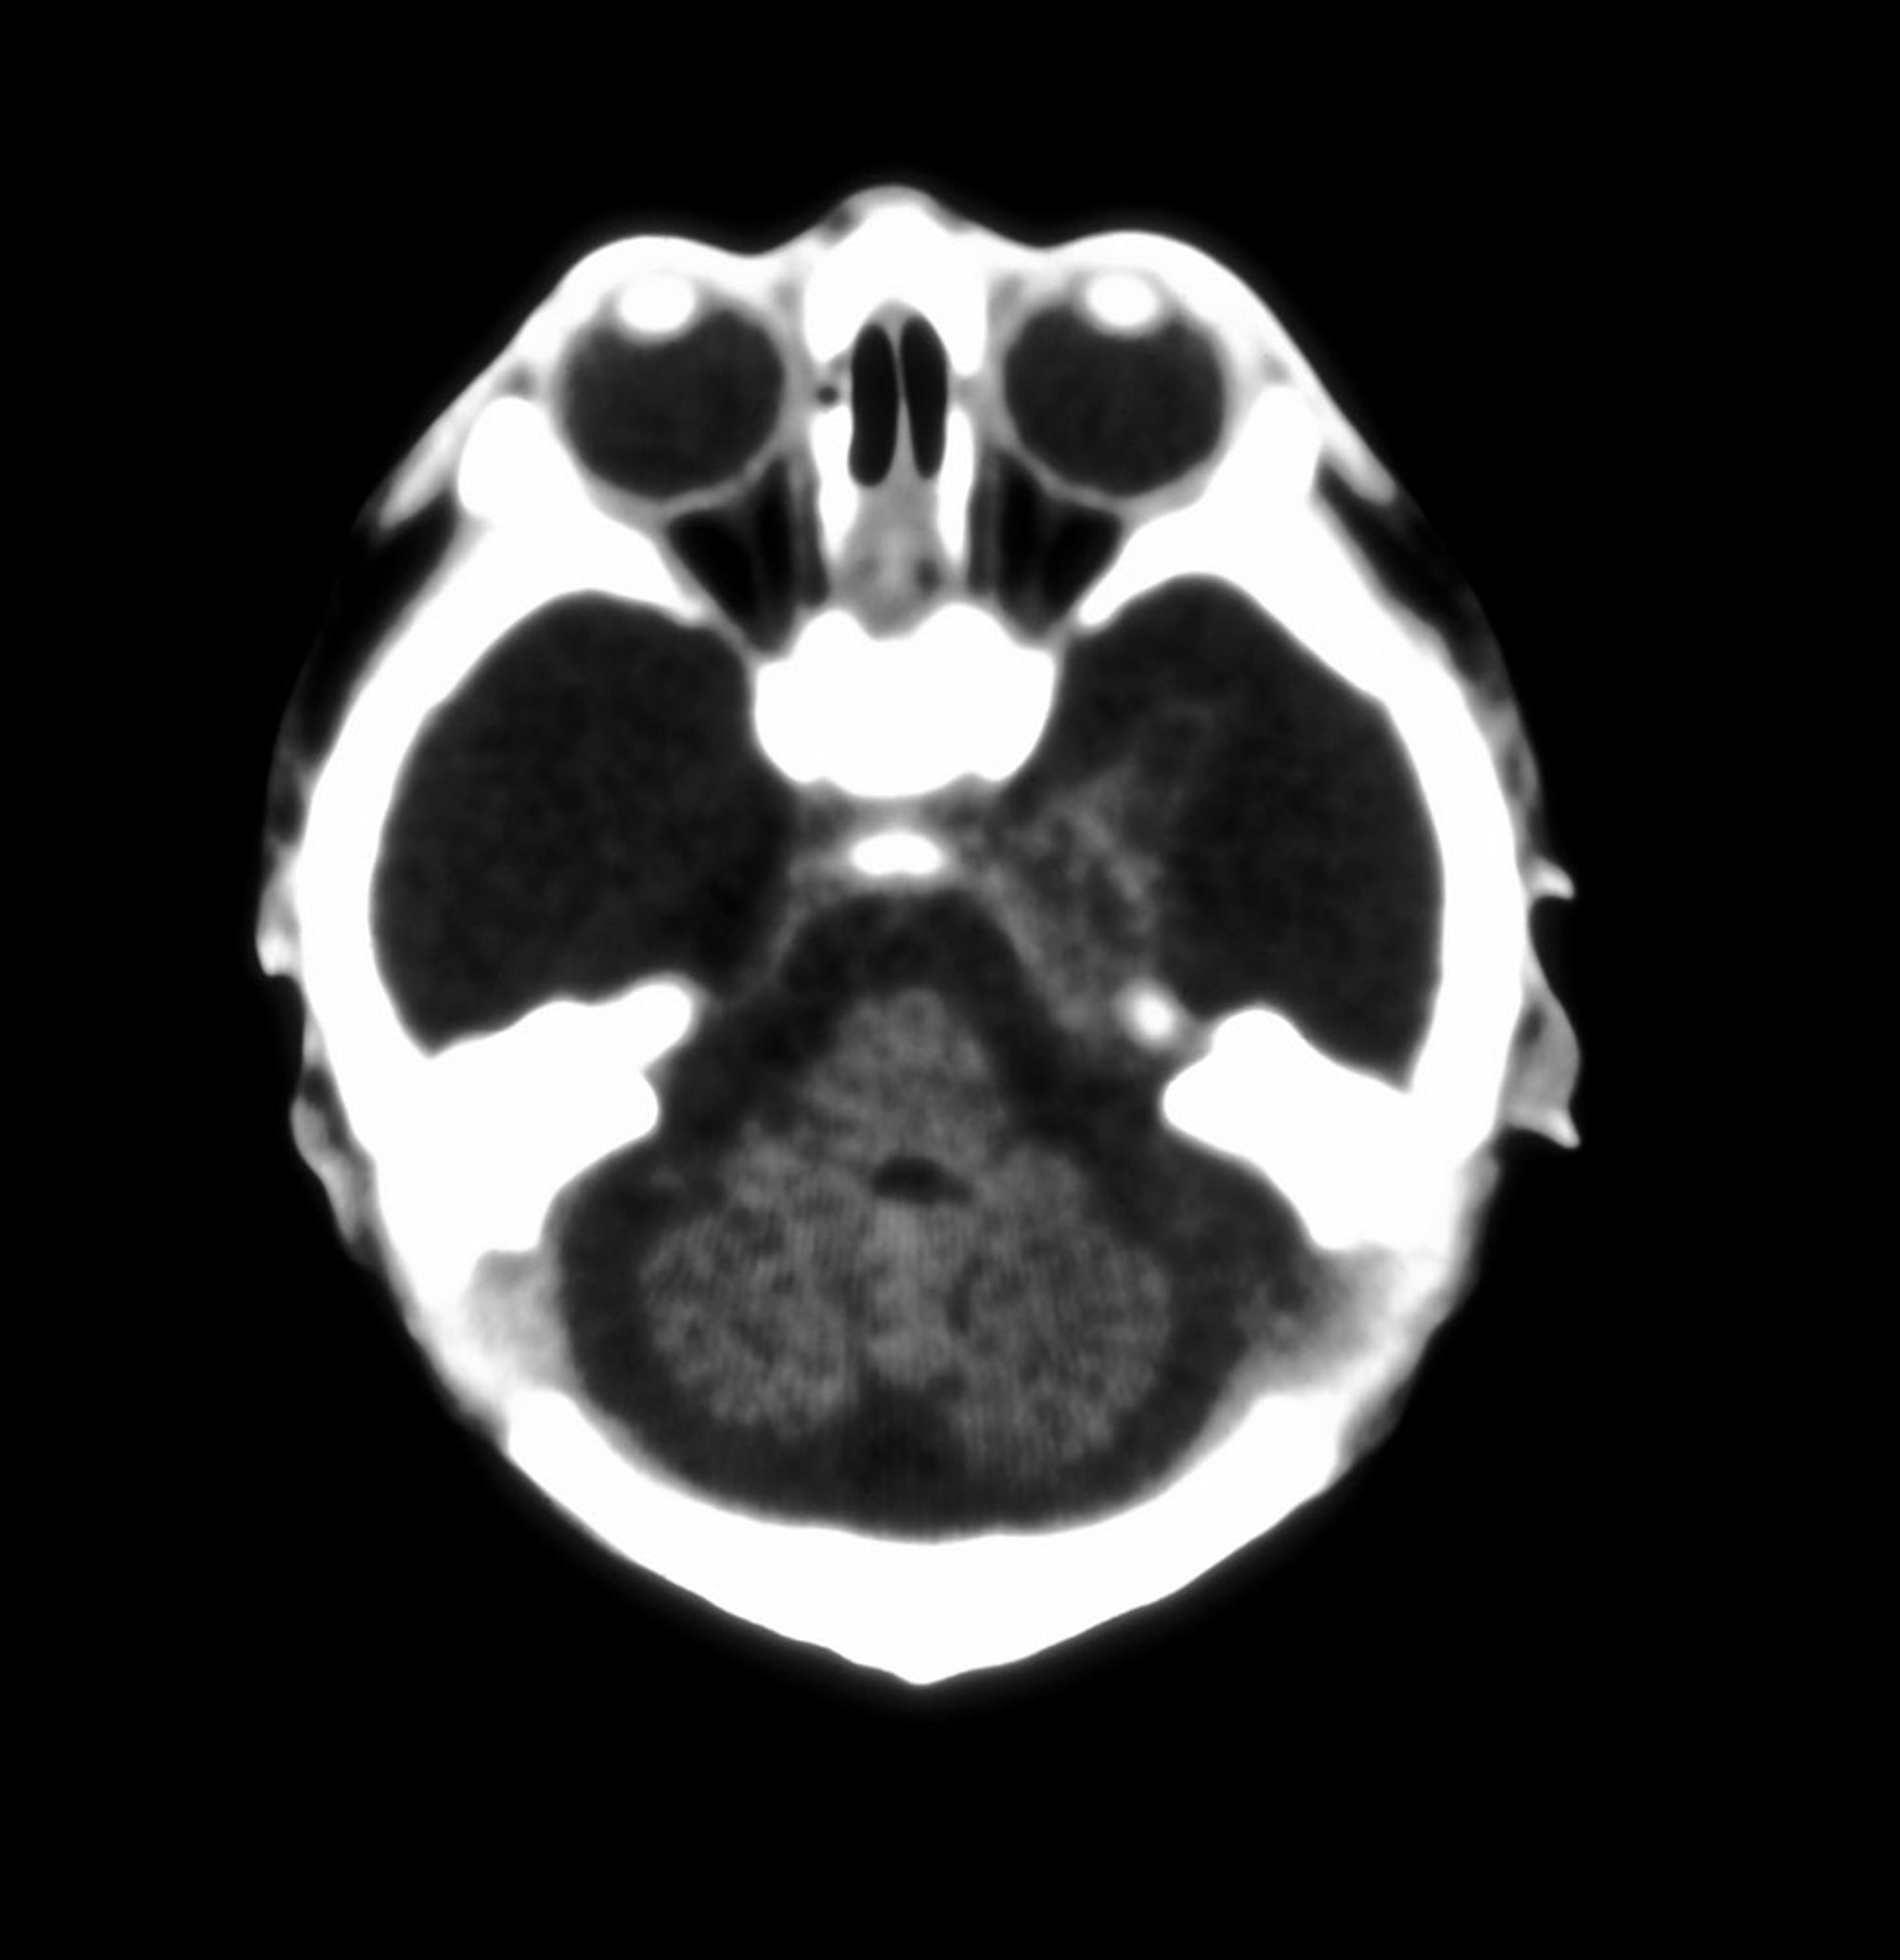

积水性无脑畸形

这张新生儿脑部的轴向CT图像显示大脑半球几乎完全缺失。